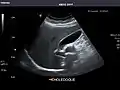

Gallbladder

Gallbladder: No stones, wall thickening, or pericholecystic fluid.

Common Bile Duct: Nondilated measuring 1.3 mm at the level of the porta hepatis.